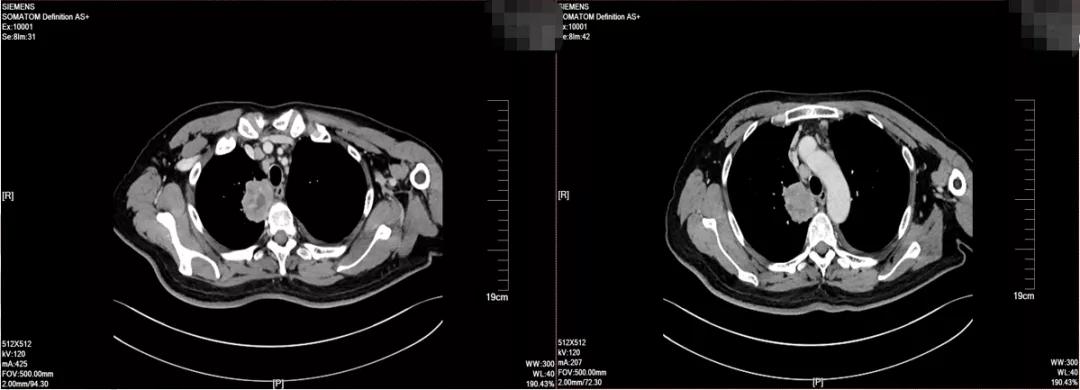

2019-10因无明显诱因下发热,于当地医院就诊,胸部CT提示:右上肺占位(5.6*4.8cm)。 考虑肺癌,伴纵膈淋巴结多发转移。

2019-10-25于广医一院行PET/CT检查考虑右上肺肺癌并右肺门、纵隔淋巴结转移。头颅MR:右侧额叶异常信号影, 考虑转移瘤。 双侧额顶叶散在缺血灶。

2019-10-25 PET/CT示右上肺癌伴纵膈多发淋巴结转移